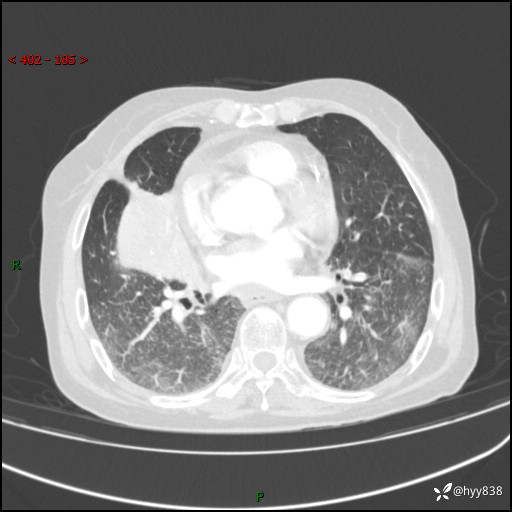

胸部CT增强(外院平扫)